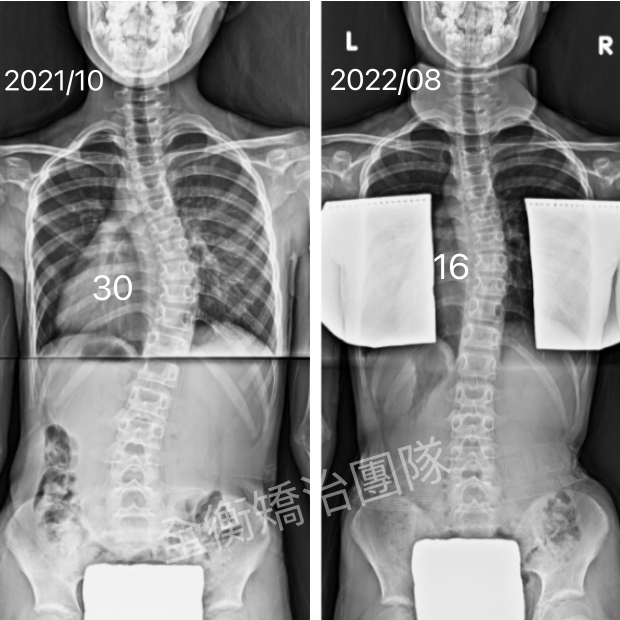

16歲女生,青春期末期才發現側彎,還有機會嗎?16歲女生,青春期末期才發現側彎,還有機會嗎?

16歲妹妹,高一健檢才發現脊椎側彎

經過一年的復健和追蹤

側彎角度由29度進步至15度,減少50%!

旋轉也從12度減少到6度 -